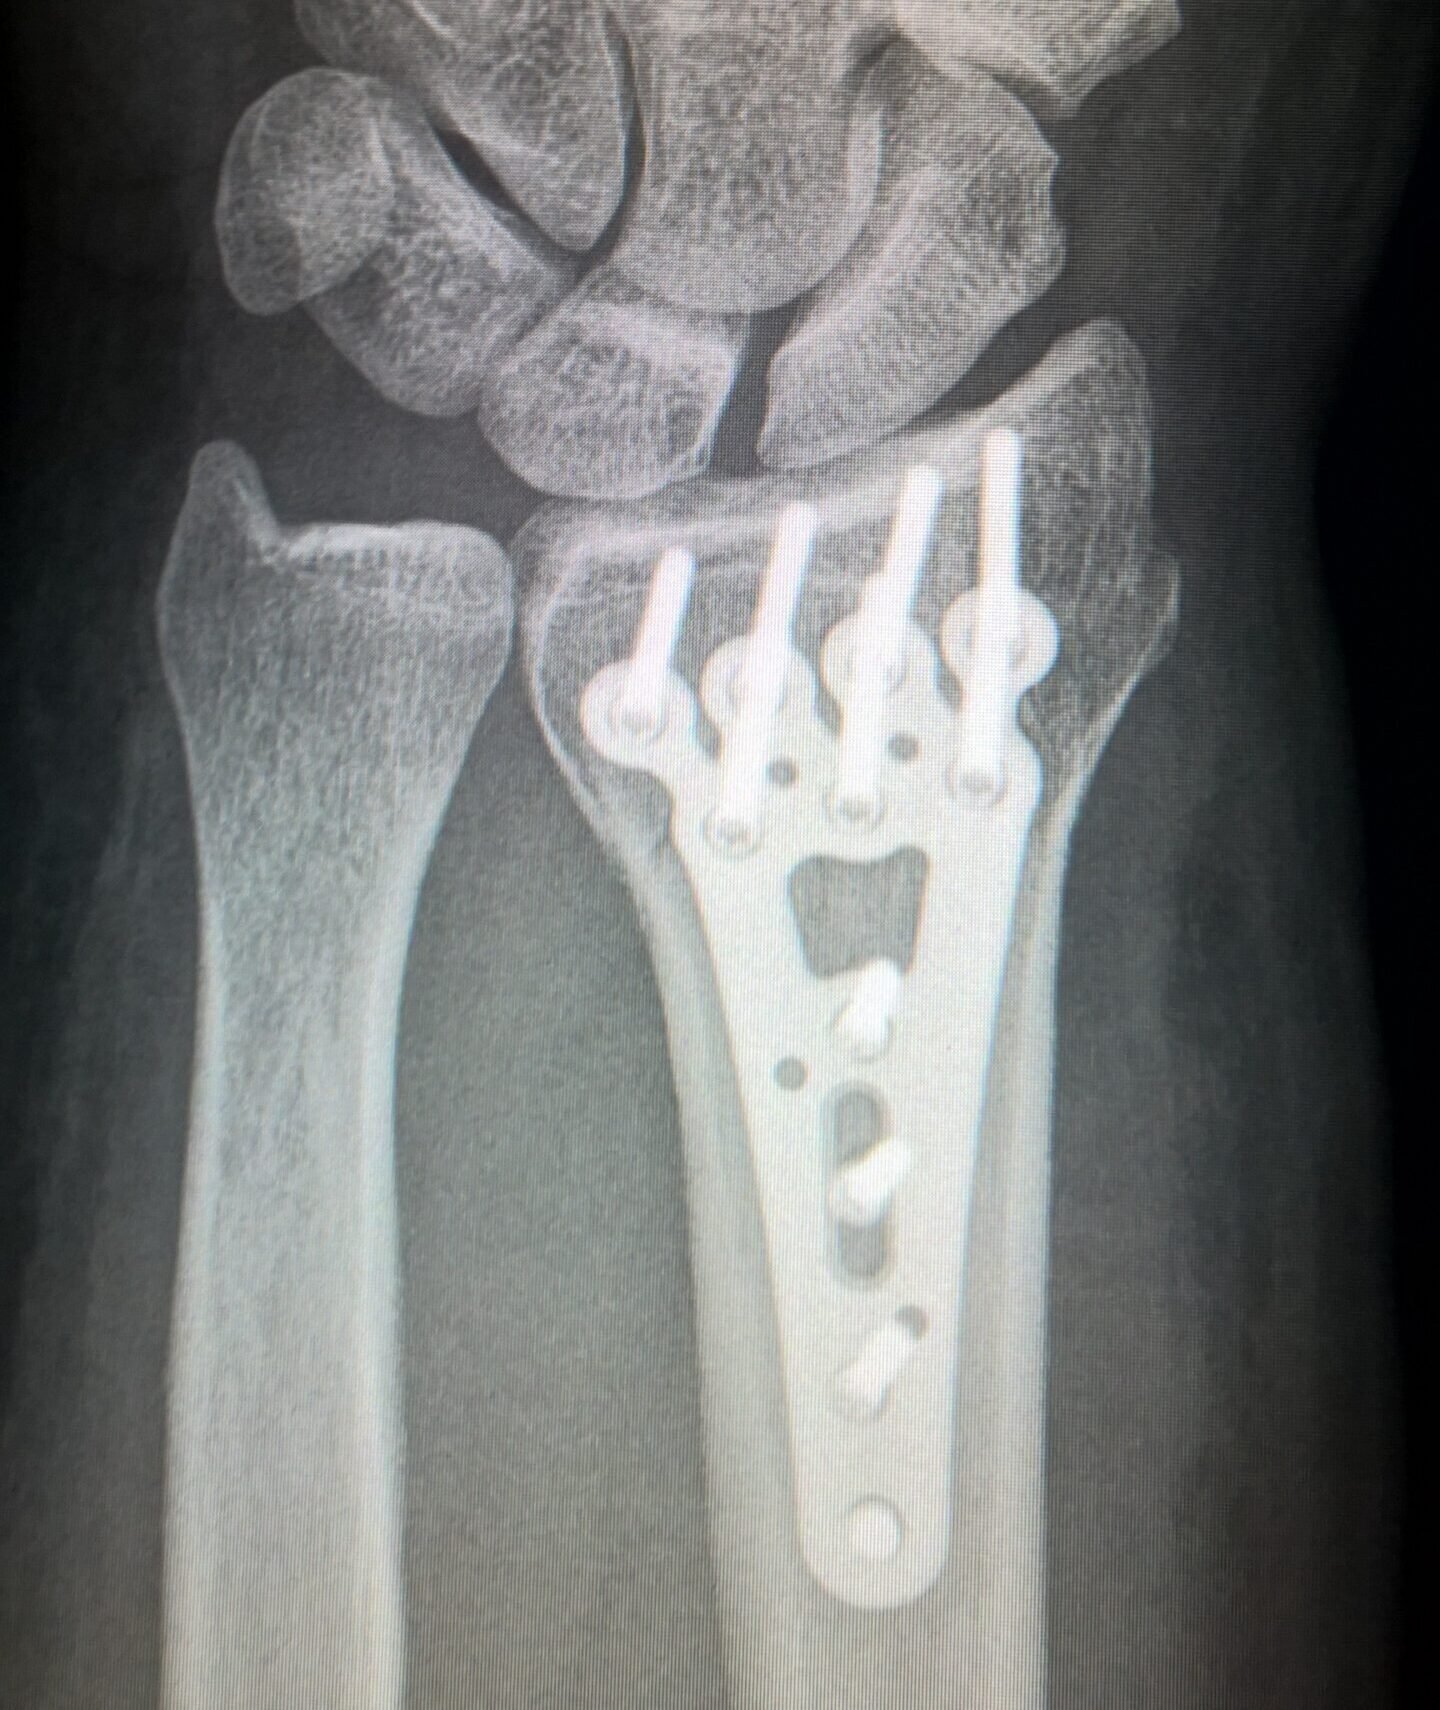

INTRAOPERATIVE

Surgical guides, custom single-use tools and any additional materials needed for the planned surgery.

broken arm 2117980